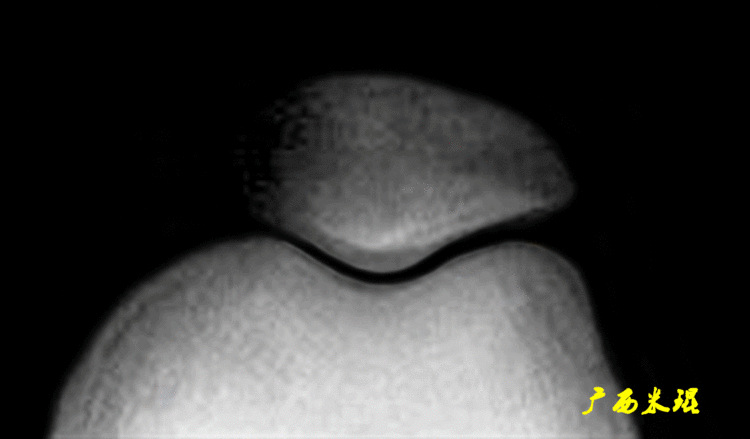

MRI检查是最常用的评估髌股关节软组织和滑车软骨的检查,在发现MPFL损伤时具有较高的敏感性和准确性,其特征性表现包括X线不能发现的软骨损伤及髌骨内侧面和股骨外侧髁的骨挫伤。MRI也可用于评估髌骨滑车指,测量髌骨高度等。